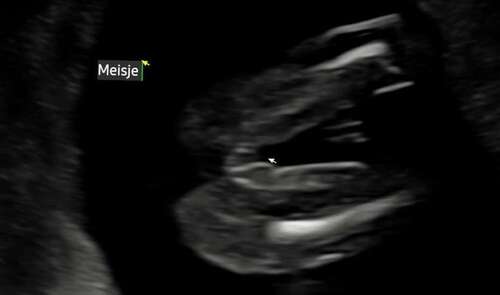

Hier even voorbeeld waar je naar moet kijken. Onderste is jou echo. Bovenst ...

Nee tenminste niet zo met 16 weken. Ik denk dat je veilig zit met een meisje😊

Ik twijfel nog omdat het bij mijn kindje iets uitsteekt met 18 weken maar wel 3 strepen heeft. Maar niks zien bij jongen is bijna onmogelijk, bijna!

Bij ons dochtertje was het ook best lastig. Daar stak het ook nog best uit bij 1 echo (bovenste). Daardoor twijfelde ik best wel. Maar door de onderste was het best duidelijk. En nubster heeft me ook gerustgesteld dat de vk het echt wel goed had😅

Ja ! Zeker een meisje

@Peterpan, in het vorige deel gaf je aan, (zowel nub als pottyshot) dat ons kindje een meisje is. Je had gelijk! :) echo gehad met 15 weken en 3 dgn. Het is een meisje volgens de echoscopist!